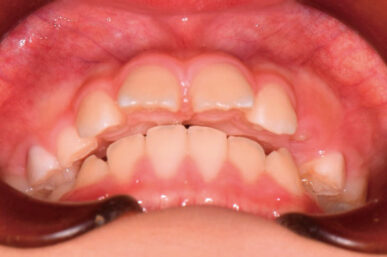

• Before

• After

出っ歯が気になるという事でしたが、下顎がさがっていました。治療開始が遅かったため生え代わりを待つ必要があり、治療期間が長くなりました。

下顎が正しい位置で噛むようになり、出っ歯に見えなくなりました。